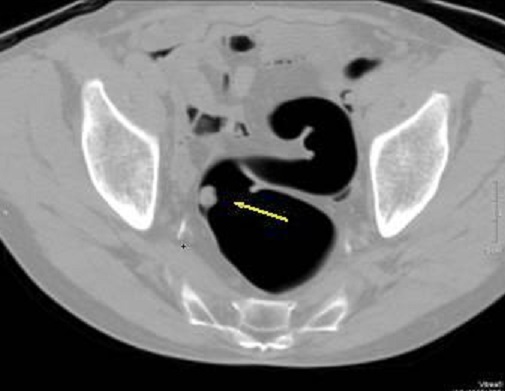

Image radiologique TDM

polyps du colon est aspect laculaire a sessile ou polypoide

a hyper-dense avec pedicule intra luminal du colon . Sa

nombreuse peut de quelque d'un au colon a multiple

Aspect du polyp

laculaire hyperdense a bord lisse et a sessile

rehaussement intraluminale du colon ( fleche blanche

) . Image TDM du polyp du colon ean coupe axiale . |

Polyp du colon sigmoide en

aspect laculaire a hyperdense situe intraluminale du colon . Sa bord est lisse et en sessile

. Image radiologique TDM en coupe axiale .a travers

S1, S2 . |